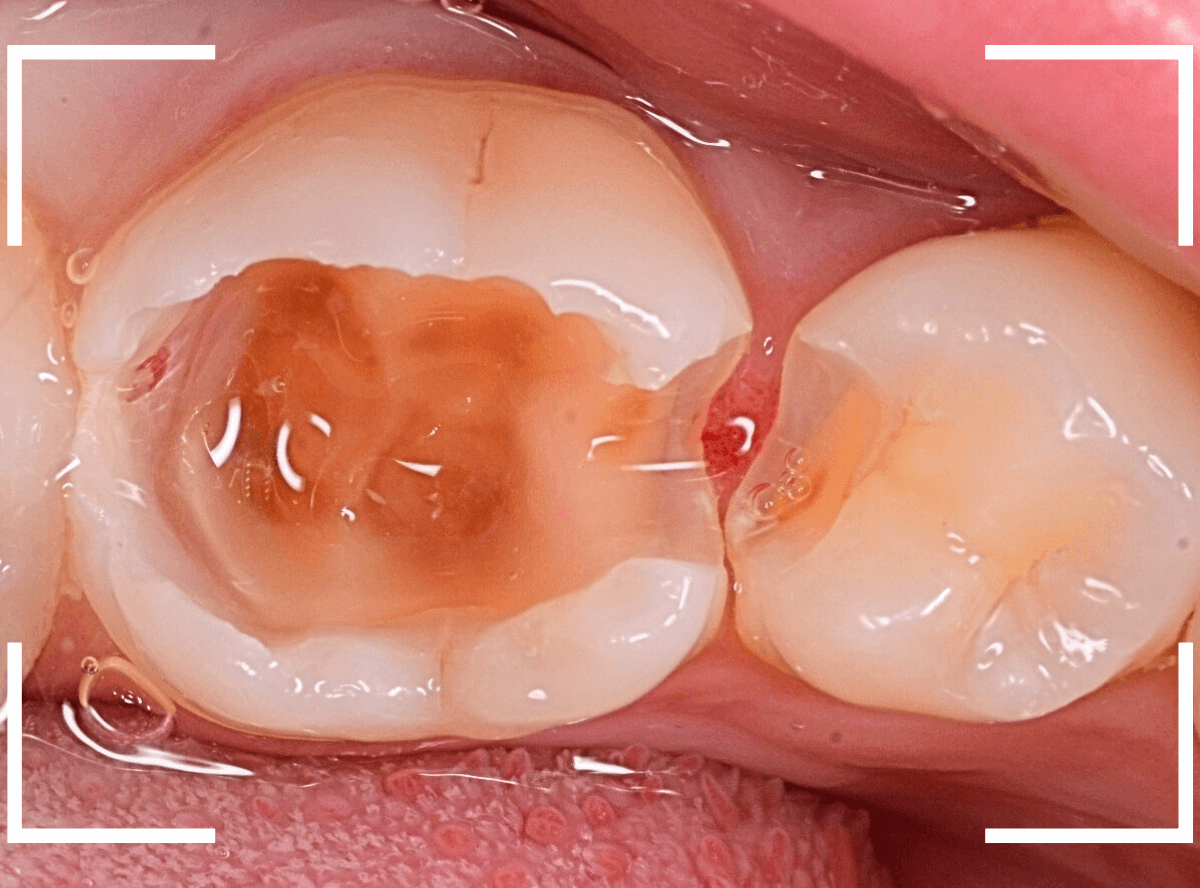

全ての虫歯を除去したところです。

神経スレスレのところまで虫歯が広がっていました。

赤く染まっている部分が、まだ虫歯が残っている箇所です。

歯の神経が近いので、余分に削りすぎないように、より慎重に虫歯を除去します。

全ての虫歯を除去しました。

奥歯は、レントゲン所見とおり、かなり深い虫歯でした。